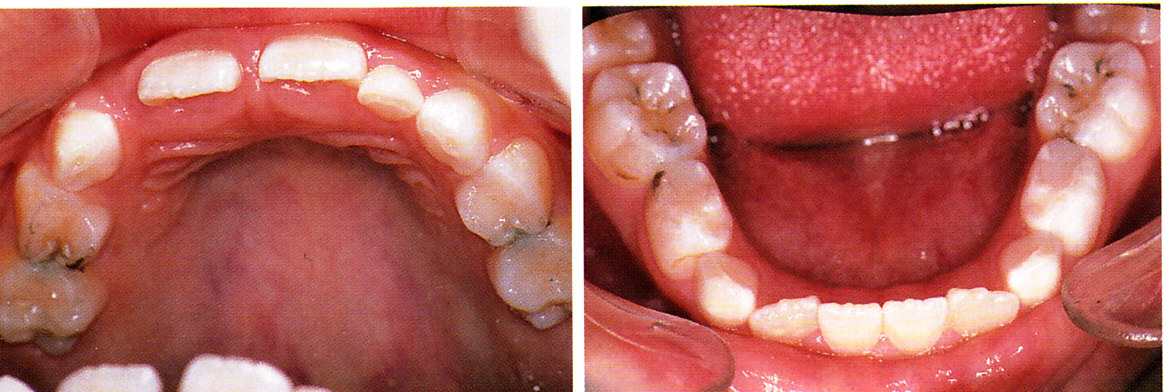

2歳 主訴の左上B左下Bの反対咬合はスルメ噛みで改善した。う蝕はまだない

4歳時の咬合面観。ハイリスクのままう蝕が発生